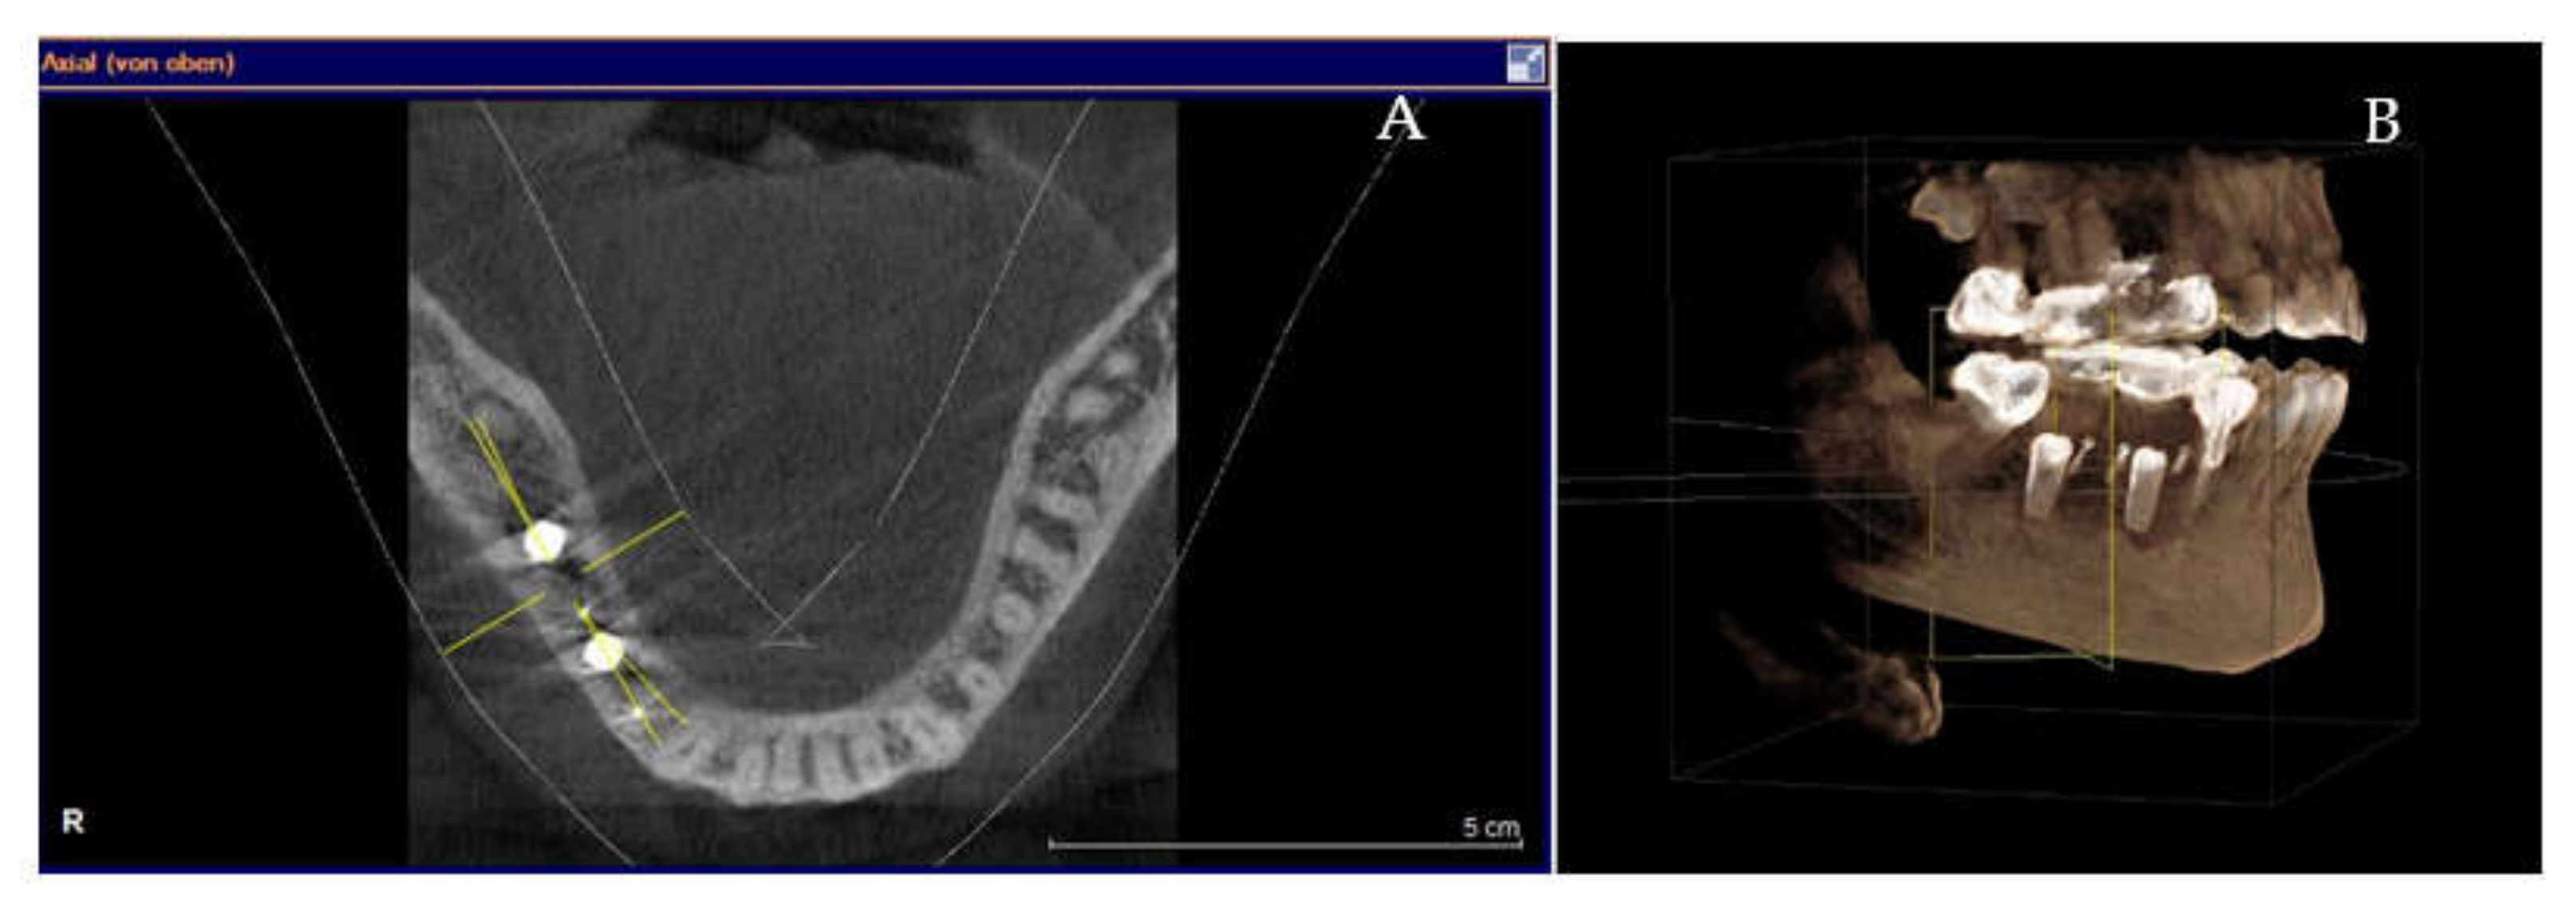

Clinical and CBCT aspects of patient from the test group, describing the stages of S-GBR technique and implant-prosthetic stage, are presented in Figure 1, Figure 2, Figure 3, Figure 4, Figure 5, Figure 6, Figure 7, Figure 8, Figure 9, Figure 10 and Figure 11. CBCT exam allows the evaluation of the horizontal alveolar bone defect and the position of the mandibular alveolar nerf (Figure 1A,B). Figure 1C,D show cross-sectional CBCT aspects of the implant sites. Figure 2 shows the narrowed mandibular alveolar bone with horizontal resorption. Figure 3 shows the exposed buccal surface of the alveolar ridge with severe horizontal resorption, after flap opening. The inserted implants (4.5 mm diameter, 11.5 mm length) and osteosynthesis screws (45° from the occlusal plan) are shown in Figure 4A. The placement of graft (autologous bone and xenograft) and collagen membrane is shown in Figure 4B. Figure 5A shows tension-free sutures, due to periosteal incisions alveolar ridge. Figure 5B shows clinical aspect at 7 months after surgery, with gingival tissue adherent on the reconstructed alveolar ridge. Figure 6 shows OPG aspect at follow-up of 7 months, with osseointegration of the dental implants. Figure 7A shows clinical aspect before osteosynthesis screws removal. Figure 7B shows clinical aspect after osteosynthesis screws removal. Figure 8A shows healthy peri-implant soft tissues. Figure 8B shows repositioning key for perfect position of abutments. Figure 10A,B show clinical aspects of implant-supported prosthetic restoration. Figure 11A,B show CBCT aspects of Osseo integrated dental implants at 24 months follow-up.

(A,B) Pre-operative CBCT aspects. (A) Narrow residual alveolar ridge. (B) Analysis of the mandibular nerve position. (C,D) Pre-operative CBCT aspects (cross-sectional).

(A,B) 7-months follow-up of S-GBR surgery. (A) CBCT shows 2 mm bone around implants. (B) CBCT shows reduced bone resorption in the coronal area of implants.

Figure 11.

(A,B) CBCT aspects (cross-sectional) of osseointegrated implants at 24-months follow-up.